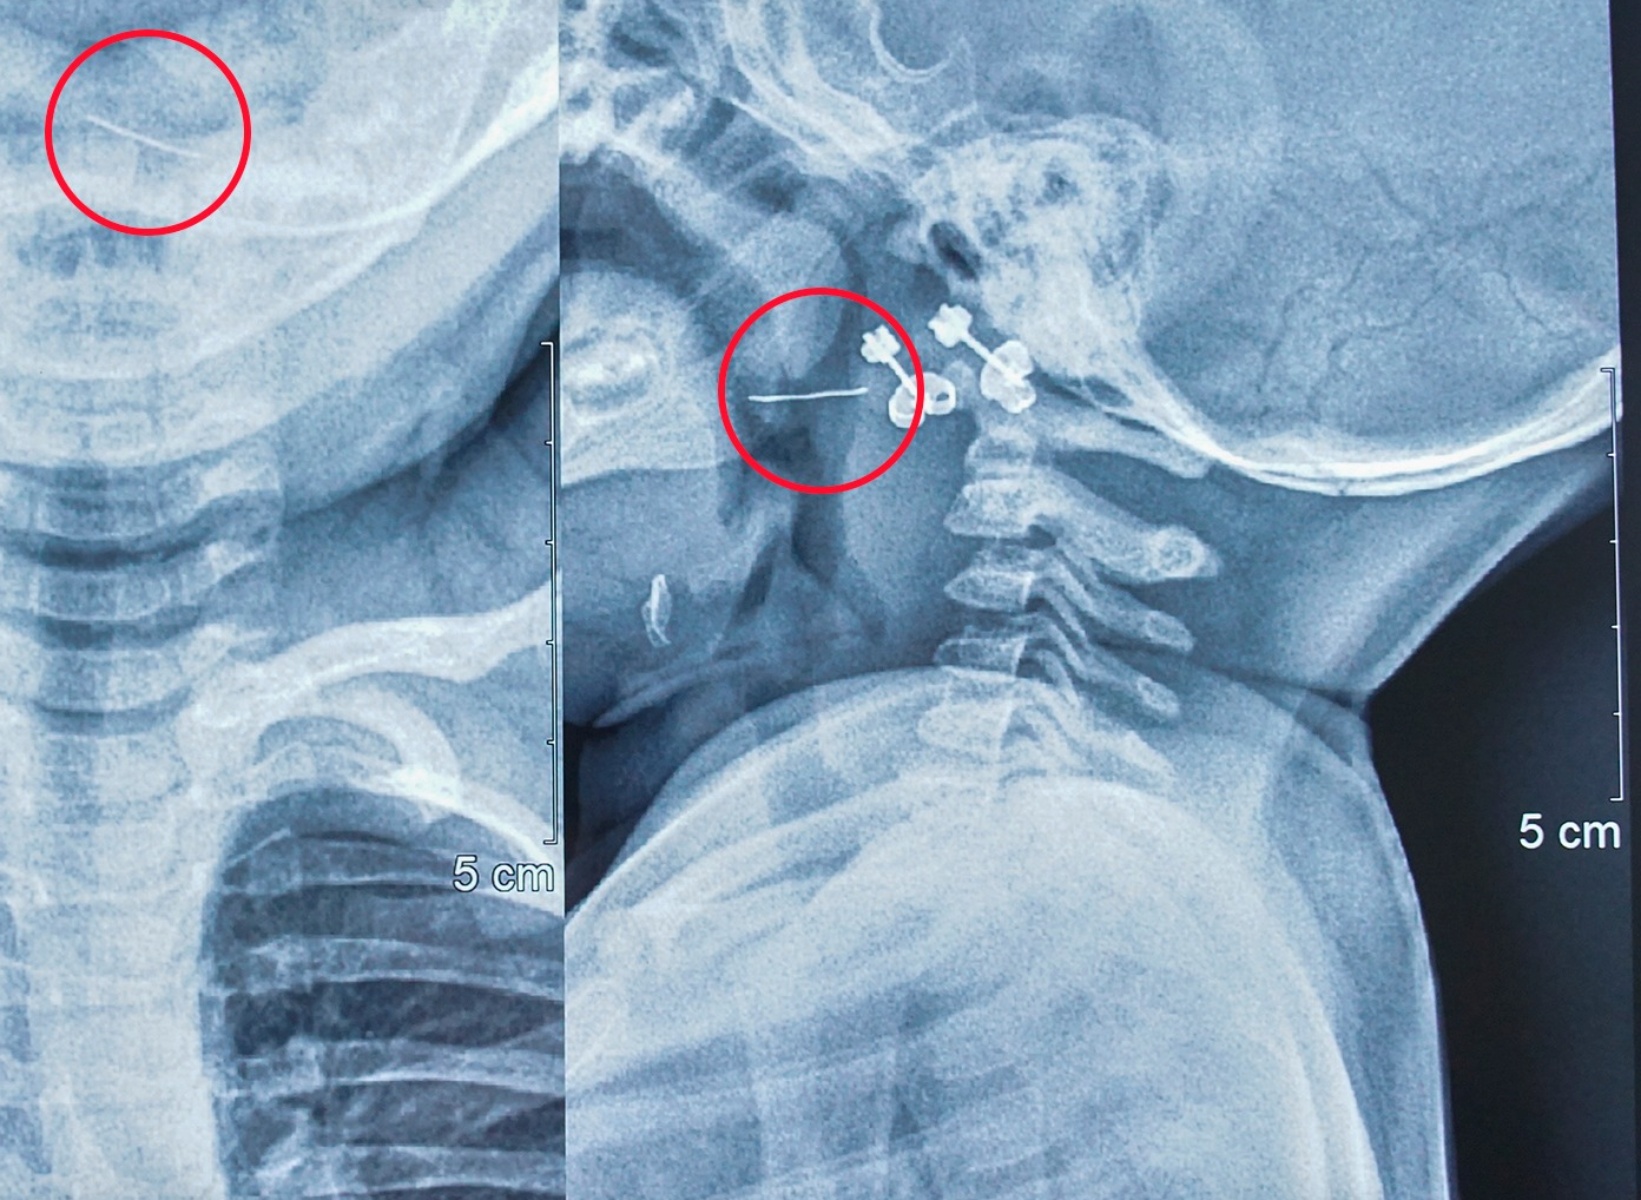

Kết quả phim X-Quang, các bác sĩ xác định có dị vật kim loại đâm xuyên qua Amidan bên trái của trẻ. (Ảnh: BV Nhi Trung ương).

Tại Bệnh viện Nhi Trung ương, sau khi trẻ được thăm khám, soi họng và đọc kết quả phim X-Quang, các bác sĩ xác định có dị vật kim loại đâm xuyên qua Amidan bên trái của trẻ.

Bác sĩ Nguyễn Khắc Trưởng, khoa Tai - Mũi - Họng, Bệnh viện Nhi Trung ương, người trực tiếp gắp dị vật cho bệnh nhi cho biết: “Nhận thấy dị vật mắc ở vị trí phức tạp, nguy cơ chảy máu cao, chúng tôi đã nhanh chóng cho trẻ làm các xét nghiệm cần thiết rồi chuyển lên phòng mổ, gây mê và tiến hành gắp dị vật lấy ra được sợi thép nhỏ nhưng rất cứng và nhọn 2 đầu, dài 2cm”.